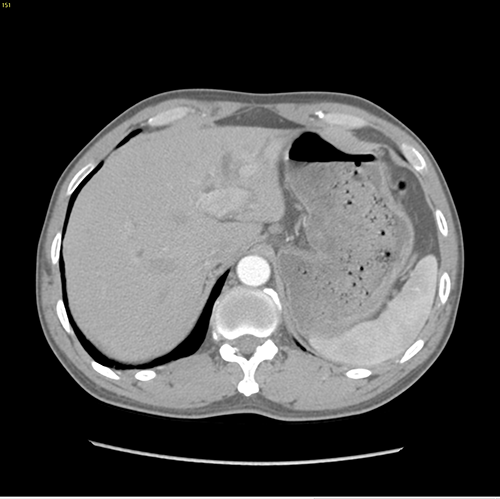

左肝管结石--左肝叶切除